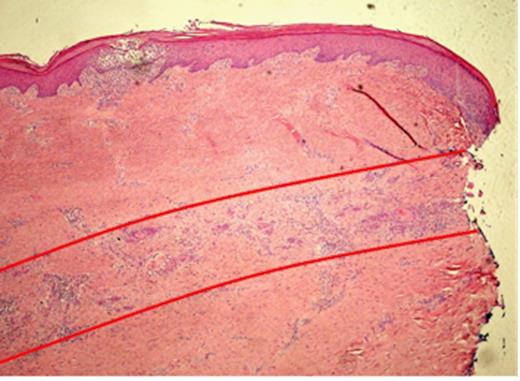

Histopathological slide of the indurated skin taken 10mm away from the ulcer showing a moderately differentiated Squamous Cell Carcinoma invading the deep dermis in a band like fashion, parallel to the epidermis (red lines). The local infiltration is well confined to the subcutaneous plane without peri-neural or deep structure involvement